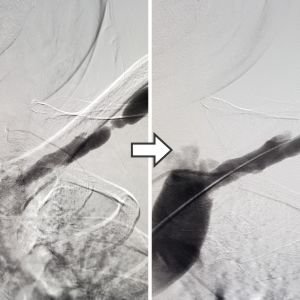

Angioembolisation For Bleeding Vessels

Minimally invasive endovascular angioembolisation using Microcatheter, Coils and Glue is a well-accepted procedure for emergencies like bleeding vessels as well as tumours.